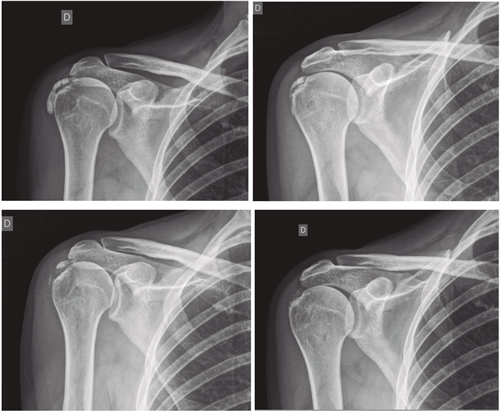

Figura 1

Figura 2